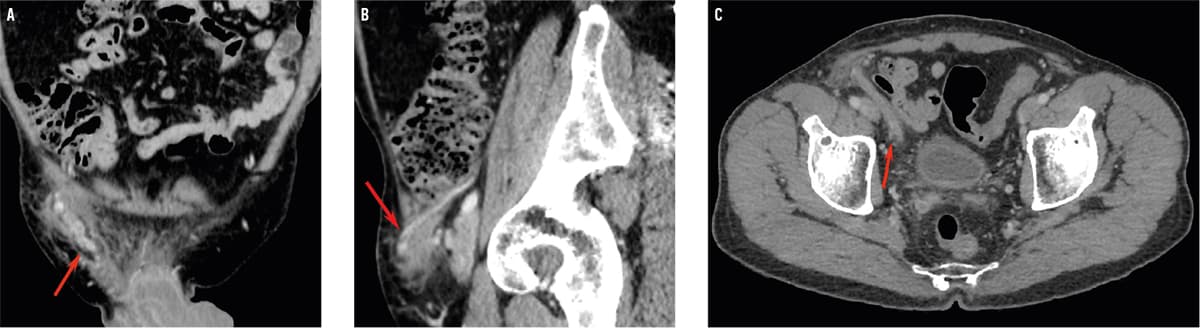

CT-billeder af abdomen med intravenøs kontrast i det koronale (A), sagittale (B) og aksiale (C) plan. Der ses opladning af højre vas deferens i canalis inguinalis med omgivende ødem og bløddelshævelse i lysken (A, B, pil). Vas deferens var dilateret intraabdominalt (C, pil). Der var desuden opladning i højre vesicula seminalis (ej vist).

En 68-årig mand blev indlagt med en tre dage varende smertefuld frembuling i højre lyske. Han var en måned forinden blevet udskrevet efter transuretral prostataresektion med postoperativ Escherichia coli-urosepsis. Over det højre ingvinale ligament fandt man en udtalt palpationsøm 2 × 7 cm rød frembuling. Scrotum og testes var upåfaldende. Pga. klinisk mistanke om inkarcereret ingvinalhernie blev der uden succes forsøgt reponering efter intravenøs indgift af morfin og diazepam. I blodprøver fandt man forhøjede niveauer af C-reaktivt protein (73 mg/l) og leukocytter (15,3 mia./l), ved urinstiks fandt man leukocyturi, og ved en senere urindyrkning påvistes E. coli. En CT af abdomen viste infektiøs vasitis. Patienten blev behandlet intravenøst med cefuroxim (750 mg x 4 dgl.) og metronidazol (500 mg x 2 dgl.) i to dage og overgik til 12 dage med peroralt givet ciprofloxacin (500 mg x 2 dgl.). Der var ingen sequelae efter tre måneder.